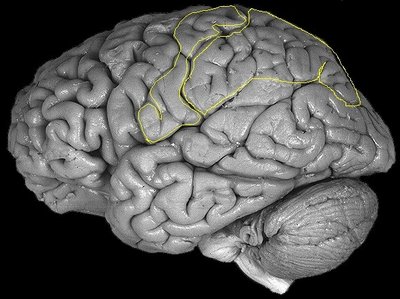

In these somatotopic maps, each body part is represented according to the degree of innervation density, e.g. body parts with higher receptor density occupy larger areas in SI (Penfield et al. 1950). Damage to SI is associated with primary discriminative tactile processing disorders, i.e. impairments in processing the physical, elementary characteristics of tactile stimuli. The posterior insular cortex also contains somatotopic maps for pain, temperature sensitivity and affective touch (Bjornsdotter et al., 2010). Higher order somatosensory processes involve wider more distributed networks, including the secondary somatosensory cortex (SII), the posterior parietal cortex and the anterior insula.

Figure 4: The insula is located beneath the frontal, parietal and temporal opercula and is involved in affective touch, pain and temperature sensitivity and in higher order tactile processing. From: the digital anatomist project in the department of biological structure at the University of Washington